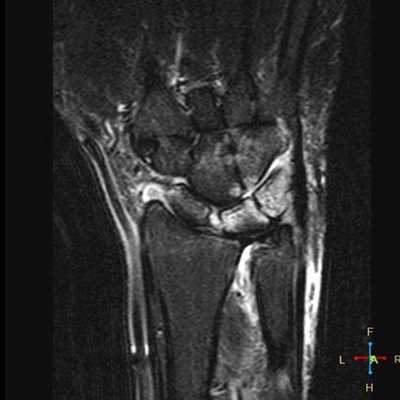

Синдром повреждения связочного аппарата

Лучевая диагностика повреждений связочного аппарата лучезапястного сустава и кисти представляет наибольшие трудности в связи со сложностью анатомии и малыми размерами данной области. Возможности рентгенографии и КТ в диагностике повреждений связок ограничены. О них судят по наличию косвенных признаков. Вследствие относительно малых размеров связок, УЗИ затруднительно. Методом выбора при исследовании связочного аппарата является МРТ.

Кистозное образование в проекции тыльных межзапястной и лучезапястной связок; незначительный синовит.